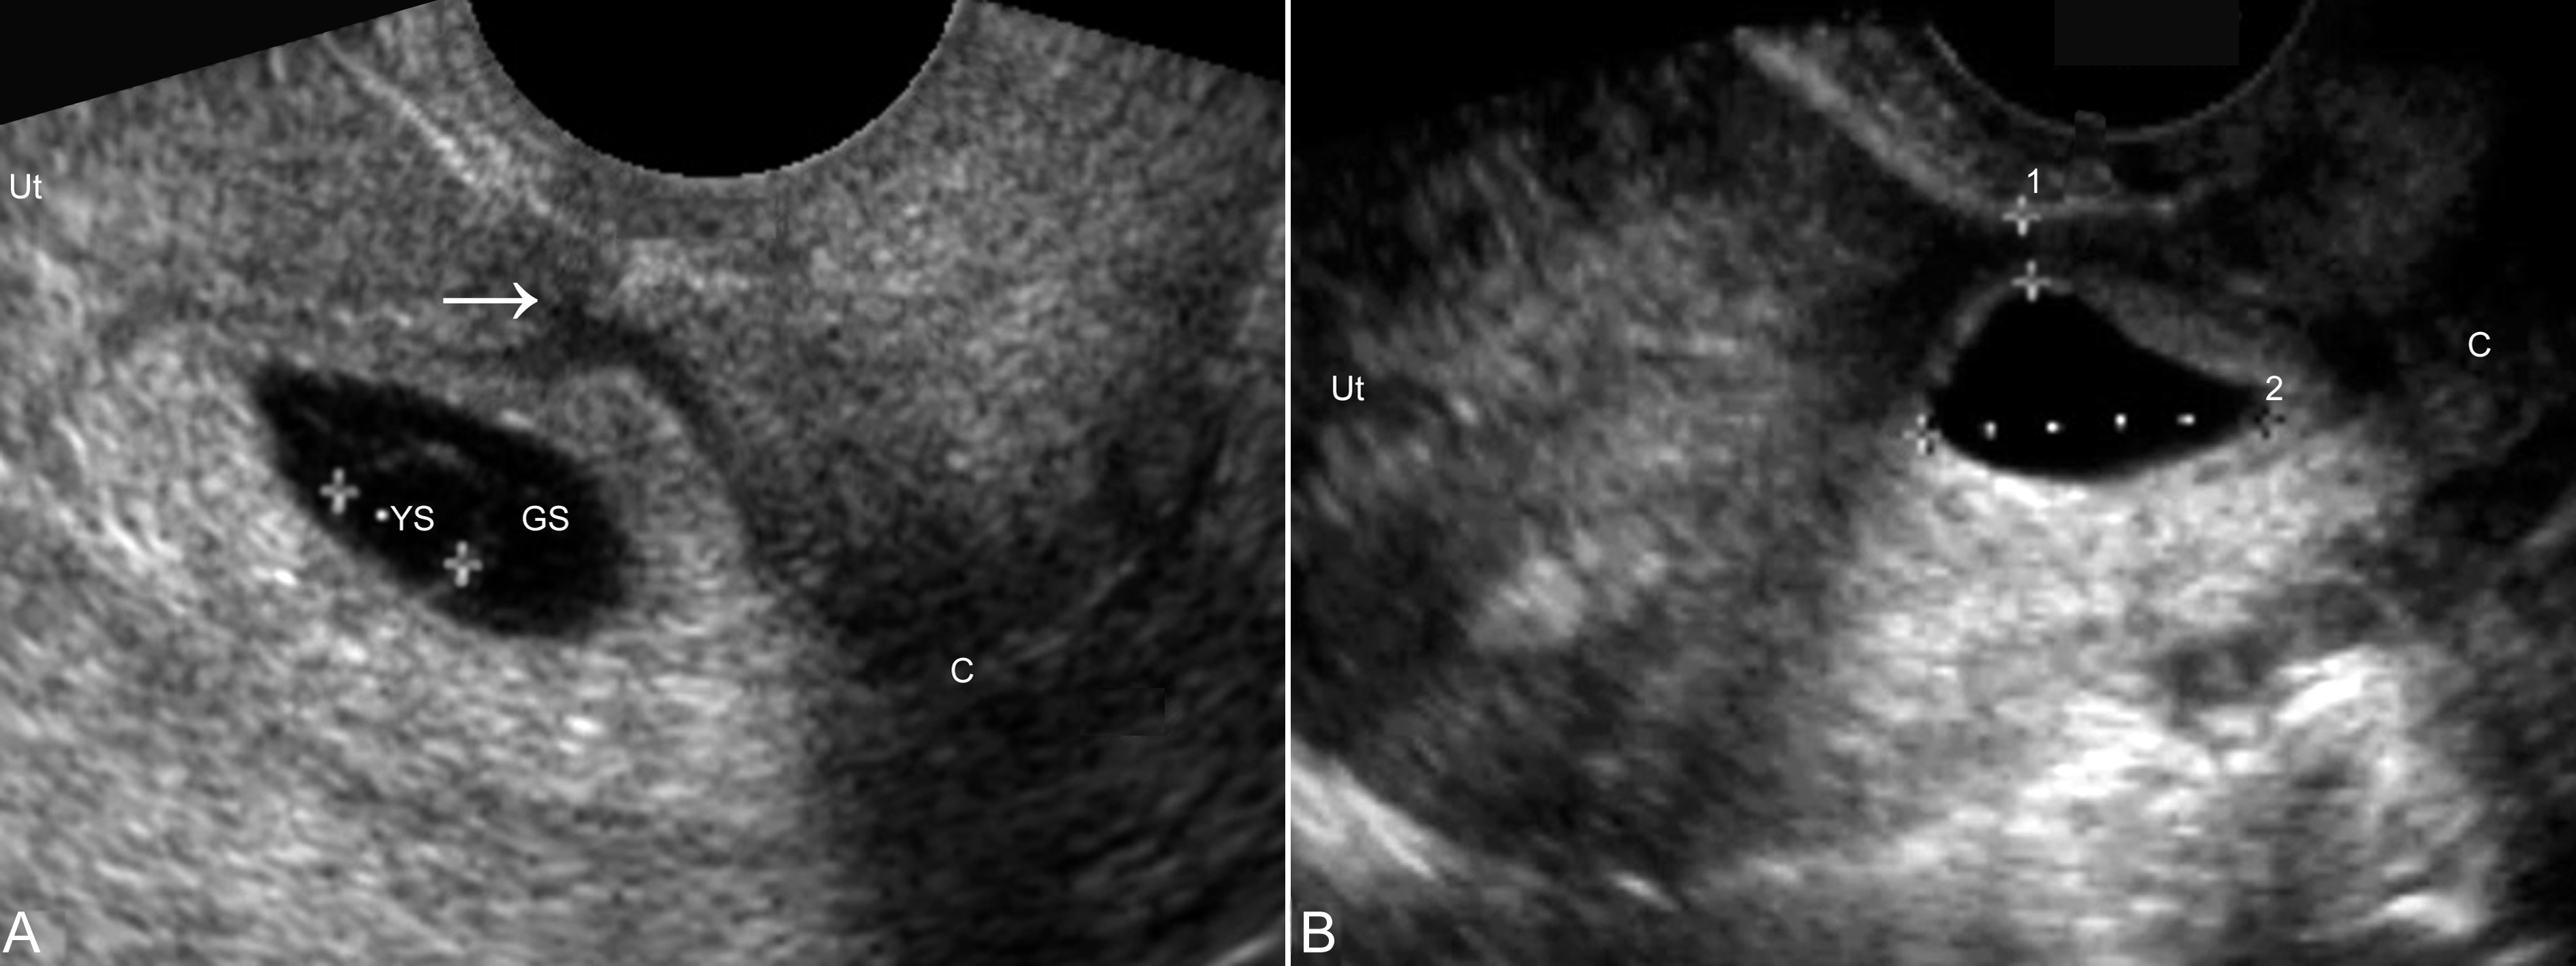

图1瘢痕子宫与瘢痕子宫妊娠

A:宫腔内显示种植于后壁的孕囊(GS)回声,内部卵黄囊(YS)内径7mm,其前方可见回声不均匀的瘢痕(箭头)。宫颈(C)显示正常

B:非孕期。子宫(Ut)前下段宫壁肌层厚度4.5mm,内部可见泪滴状无回声,提示瘢痕憩室形成